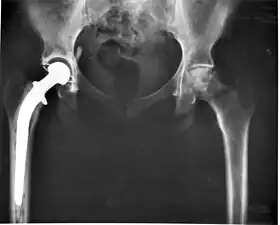

Medical implants

An implant is a kind of medical device made to replace and act as a missing biological structure (as compared with a transplant, which indicates transplanted biomedical tissue). The surface of implants that contact the body might be made of a biomedical material such as titanium, silicone or apatite depending on what is the most functional. In some cases, implants contain electronics, e.g. artificial pacemakers and cochlear implants. Some implants are bioactive, such as subcutaneous drug delivery devices in the form of implantable pills or drug-eluting stents.

- Class III devices generally require premarket approval (PMA) or premarket notification (510k), a scientific review to ensure the device's safety and effectiveness, in addition to the general controls of Class I. Examples include replacement heart valves, hip and knee joint implants, silicone gel-filled breast implants, implanted cerebellar stimulators, implantable pacemaker pulse generators and endosseous (intra-bone) implants.